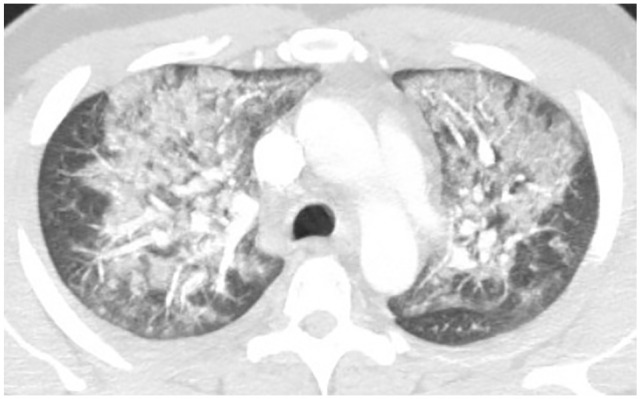

1). Initial CXR showed left basilar infiltrate and she was started on levofloxacin for presumed pneumonia. Her respiratory status declined over the next few days and CTA of chest later showed bilateral upper lobe ground glass opacities (Figure 4). Airway examination was normal on bronchoscopy and BAL gram stain showed mixed respiratory flora and cultures were negative for bacterial, fungal, and viral pathogens. BAL differential showed 60% neutrophils, 30% lymphocytes, and 10% macrophages. Given negative infectious workup, no other etiology identified for respiratory failure and imaging consistent with VALI from CBD/THC vaping, she was initiated on 60 mg of IV methyl prednisone daily and switched to 40 mg of oral prednisone 2 days later. Her symptoms subsequently resolved, and she was sent home on room air with a tapering steroid course over 2 weeks.